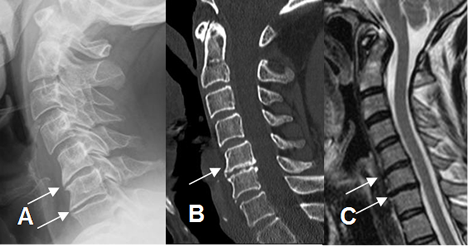

Fig 32. Cambios degenerativos del disco.

A: Rx lateral, B: TAC reconstrucción sagital y C: RM sagital en T2. Disminución de los espacios intervertebrales, por proceso degenerativo.